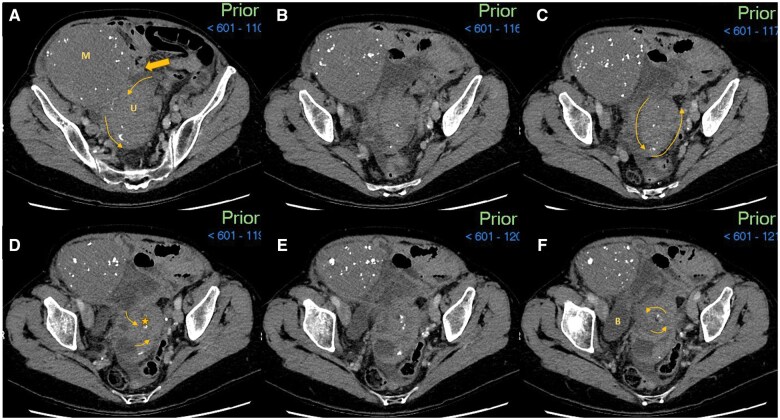

This case report describes the rare occurrence of a pre-operative radiological diagnosis of uterine torsion in the non-gravid uterus. A 78-year-old female presented with a 5-day history of worsening non-specific gastrointestinal symptoms. Her admission CT study initially reported a large adnexal mass lesion causing obstruction of neighbouring small bowel loops. Management was initiated under the presumption of a complex uterine fibroid causing local small bowel obstruction. Only a secondary radiological review-conducted due to persistent abdominal pain-identified the characteristic "whirlpool" sign of the uterine cavity and prompted the differential of uterine torsion. Contrast-enhanced MRI study further confirmed this suggestion with a lack of uterine contrast uptake and the "X-sign." The patient subsequently had an emergency laparotomy for a total abdominal hysterectomy and bilateral salpingo-oophorectomy. Intra-operative findings and further histological analysis demonstrated a distorted uterine cavity with haemorrhagic infarction, confirming a diagnosis of uterine torsion.